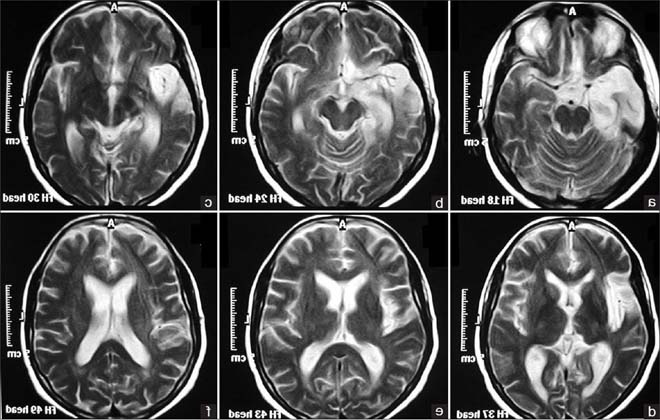

Не секрет, що головний мозок споживає 2/3 поживних речовин і кисню, які надходять в організм людини ззовні. В силу різних факторів процеси кровопостачання всередині черепа можуть порушуватися – у тканинах з’являються вогнища ішемії, в яких гинуть клітини. Подібний стан і називається енцефалопатією.